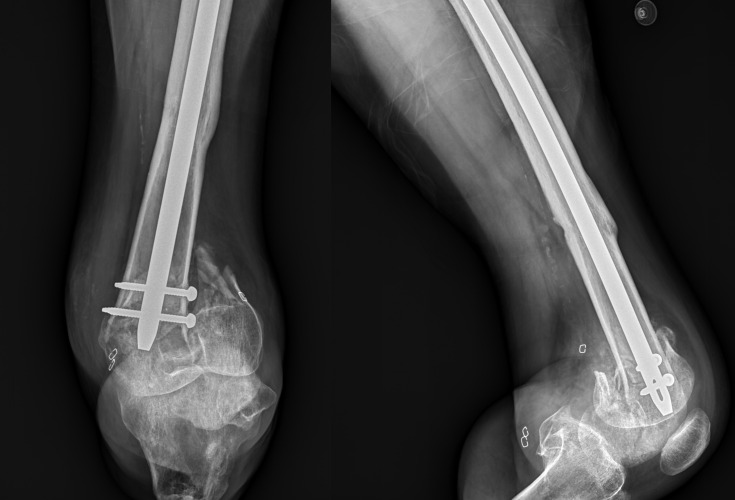

The management of retained orthopedic hardware during amputation procedures presents significant challenges. A case utilizing a modified Gritti-Stokes through-knee amputation to address a periprosthetic fracture with an exposed intramedullary nail (IMN) in a patient with multiple comorbidities is reported. A 47-year-old male with a history of human immunodeficiency virus, hepatitis C virus, and type 2 diabetes mellitus presented with a left femoral periprosthetic supracondylar fracture. The patient had an existing IMN from a previous femoral shaft fracture 20 years prior, along with a left below-knee amputation. Due to the newly occurred periprosthetic fracture and the patient's immunocompromised status, further amputation was deemed necessary. However, removal of the well-integrated IMN posed significant risks. A modified Gritti-Stokes through-knee amputation was performed, adapting the procedure to use the patella as a biological cap to cover the exposed IMN tip. At 4-month follow-up, the patient demonstrated satisfactory wound healing and stable positioning of the patellar cap. The patient achieved ambulation with an above-knee prosthesis and crutch assistance, reporting high satisfaction and no pain or discomfort. This case highlights the versatility of the Gritti-Stokes procedure in addressing complex scenarios involving retained hardware. By utilizing the patella as a biological cover for the exposed IMN, the risks associated with hardware removal was avoided while achieving a stable, well-healed amputation stump. This modification of the Gritti-Stokes technique offers a viable solution for patients with retained IMNs requiring through-knee amputation, particularly in cases where hardware removal is contraindicated or highly risky.